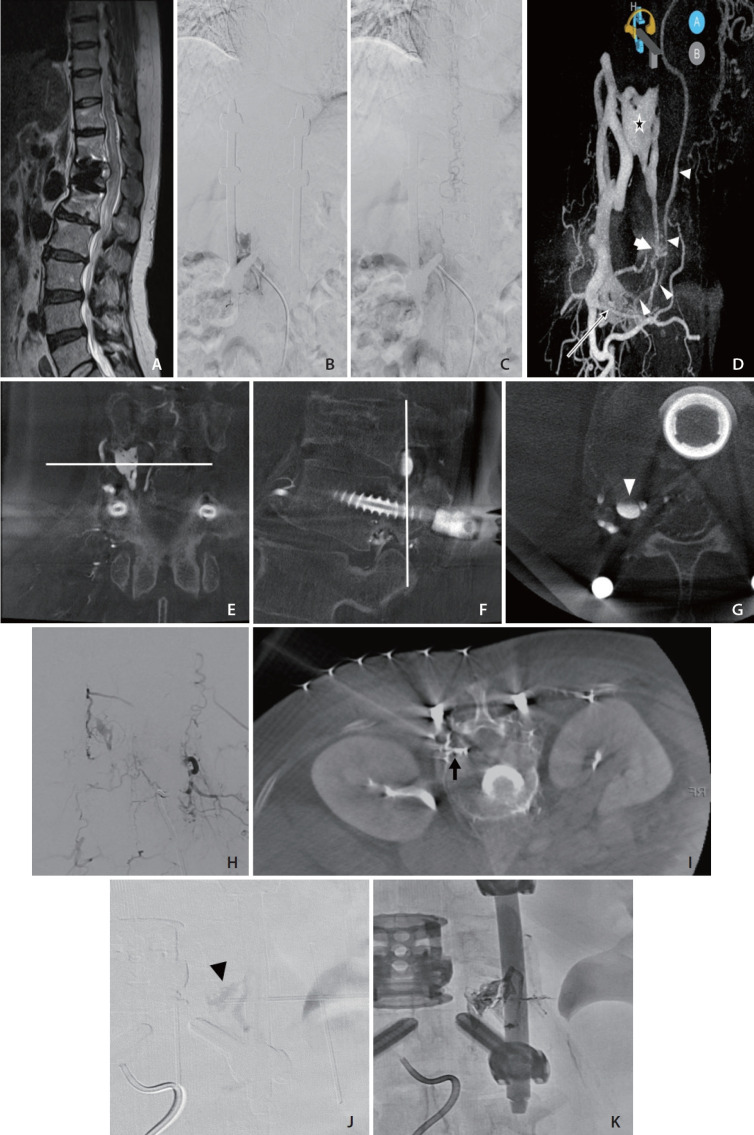

We present a case of a patient in their 50s with a spinal epidural arteriovenous fistula (SEDAVF) at L2 level with intradural venous reflux. Initial transarterial embolization was attempted but failed due to vessel tortuosity and vasospasm. The second embolization was carried out with percutaneous puncture of the epidural venous sac under cone-beam computed tomography angiography (CBCTA) guidance. Following the complete obliteration of the fistula, resolution of the venous congestion and significant improvement of the patient's symptoms were achieved. This case highlights the utility of the percutaneous approach as an alternative treatment strategy for SEDAVFs when traditional endovascular routes are not feasible. Advanced imaging techniques, such as CBCTA, facilitate precise navigation and successful embolization.